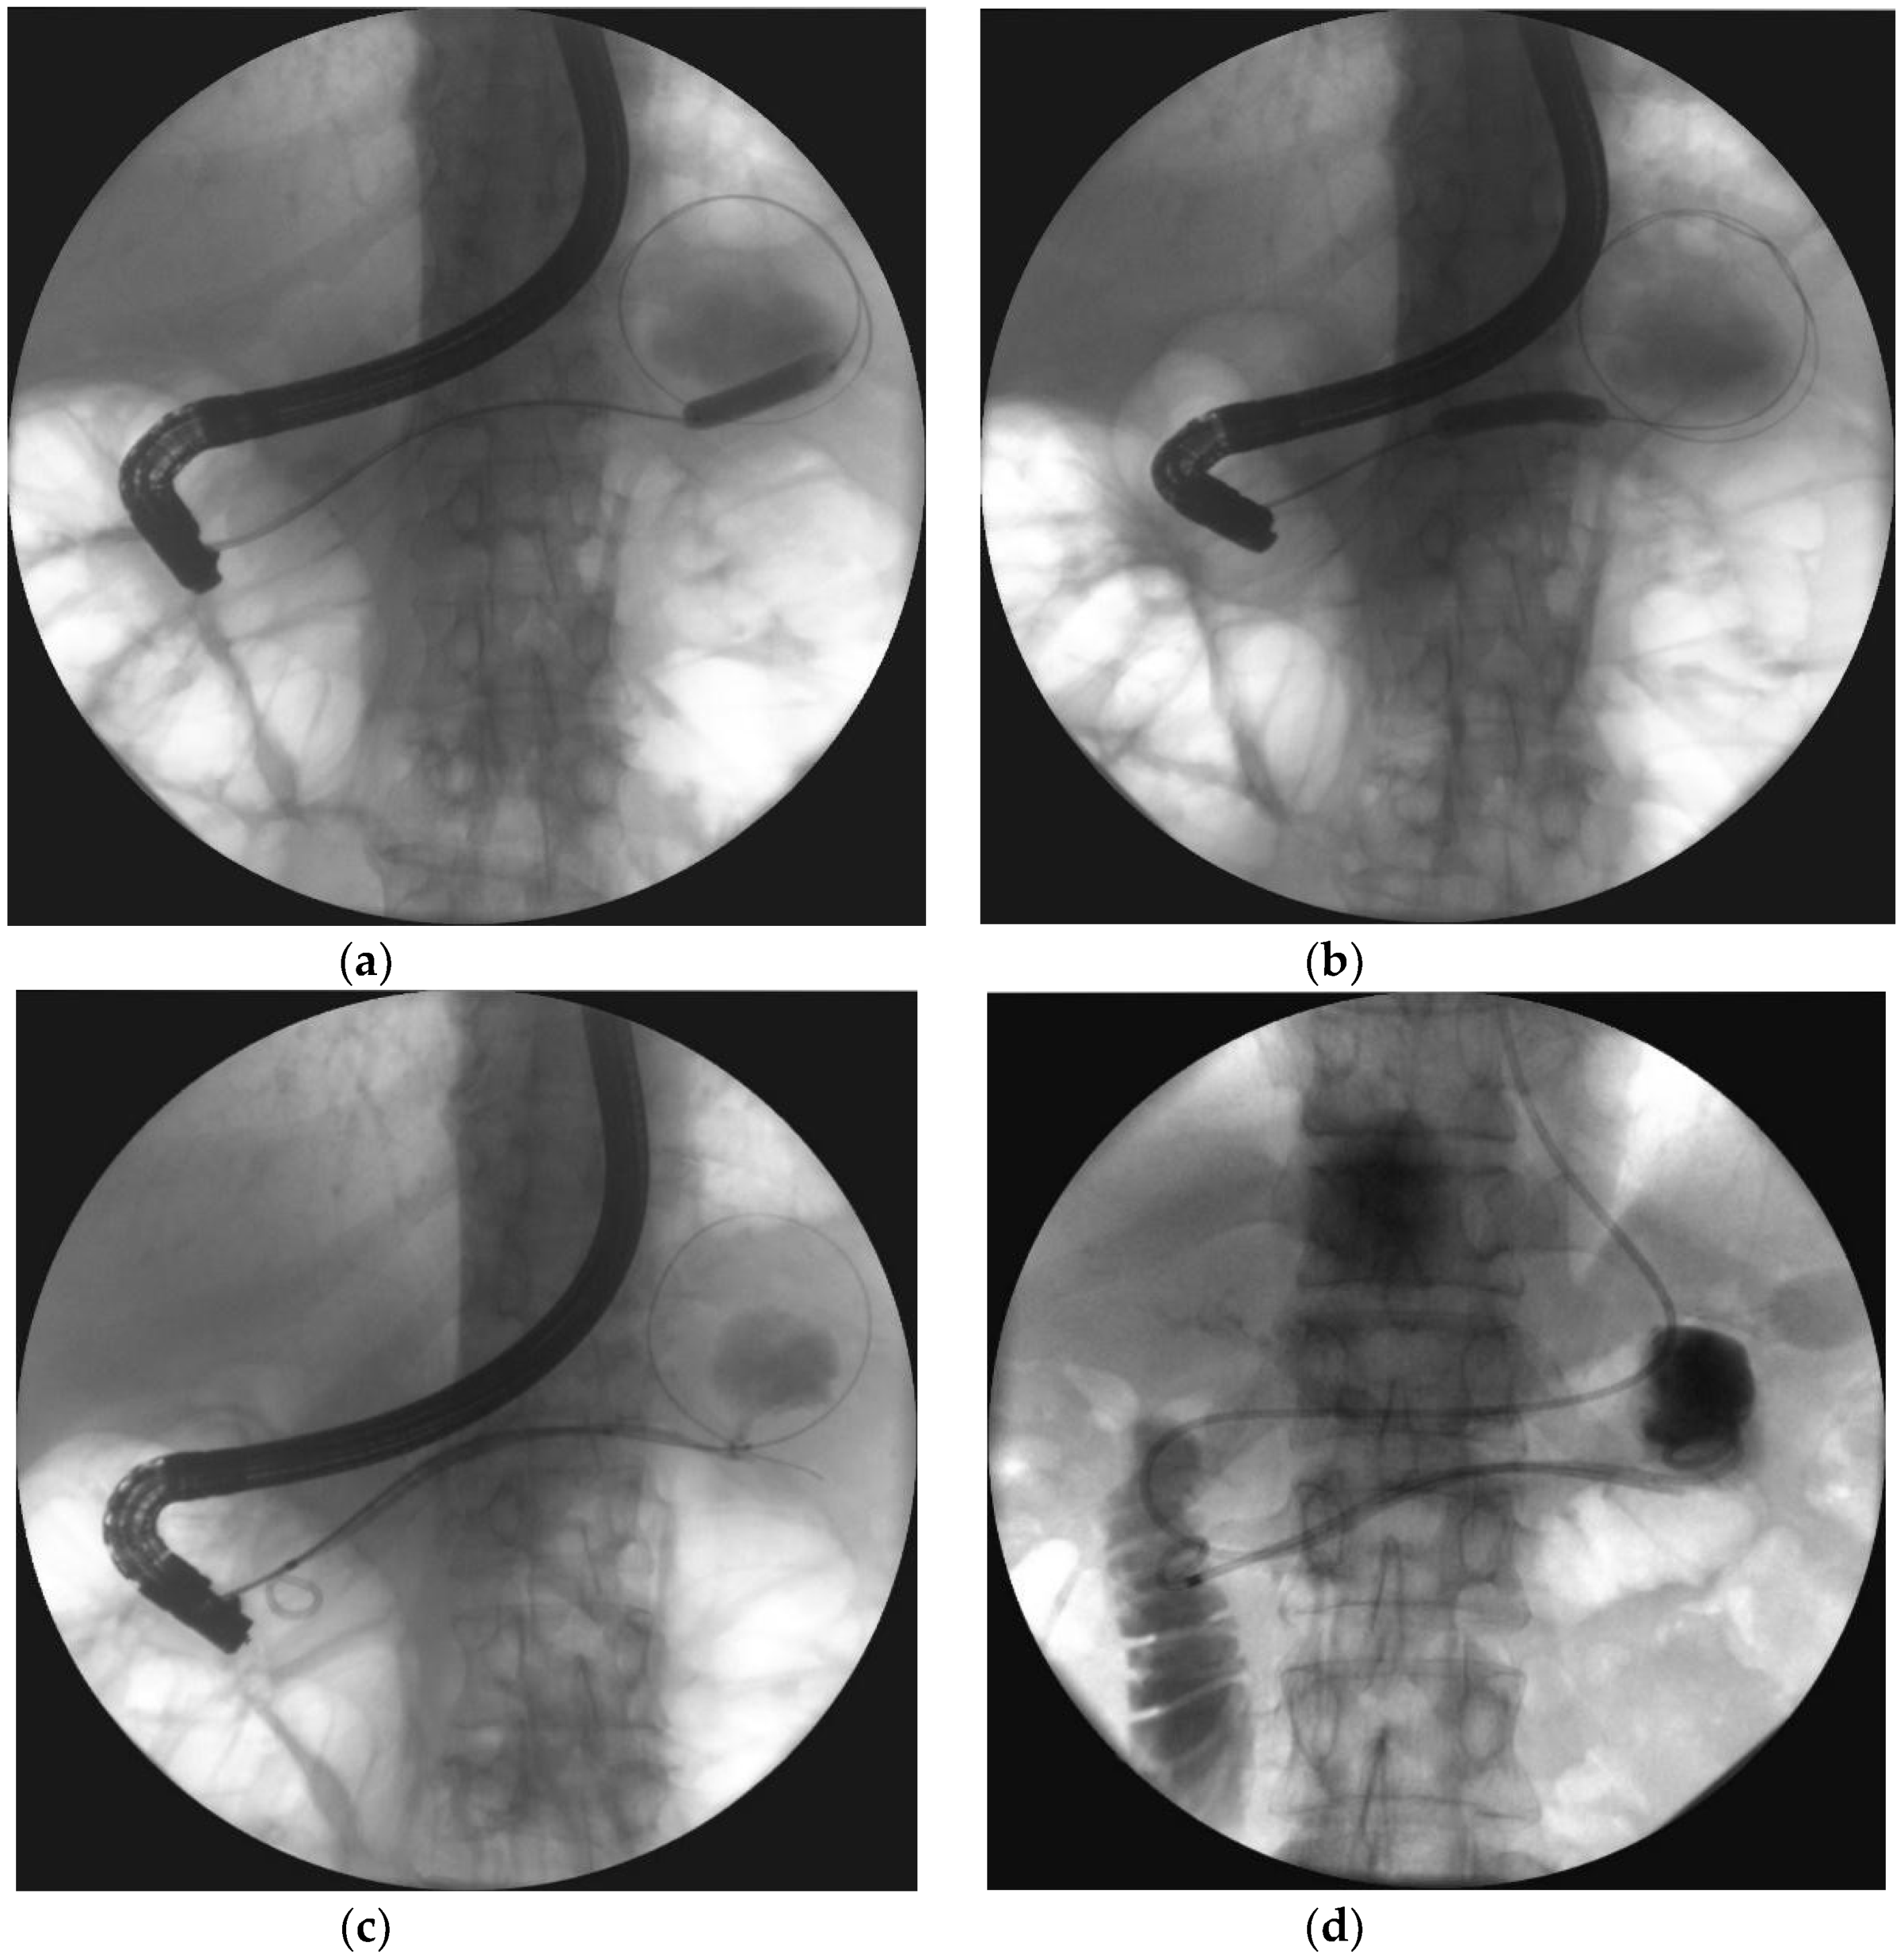

- Varadarajulu, S.; Phadnis, M.A.; Christein, J.D.; Wilcox, C.M. Multiple transluminal gateway technique for EUS-guided drainage of symptomatic walled-off pancreatic necrosis. Gastrointest. Endosc. 2011, 74, 74–80. [Google Scholar] [CrossRef]

- Jagielski, M.; Smoczyński, M.; Adrych, K. Endoscopic treatment of multilocular walled-off pancreatic necrosis with the multiple transluminal gateway techniques. Wideochir. Inne. Tech. Maloinwazyjne. 2017, 12, 199–205. [Google Scholar] [CrossRef] [PubMed]

| Multiple transluminal gateway technique (MTGT) | The creation of multiple transmural tracts between the gastrointestinal lumen and the WON cavity. In MTGT another transmural tract between the necrotic cavity and the gastrointestinal lumen was performed in case of multilocular necrotic collections divided by septa. |

| Single transluminal gateway transcystic multiple drainage (SGTMD) | Additional transmural drainage of extensive necrosis through a single fistula. Stents and nasocystic drains were introduced in the subcavities of WOPN through the single transmural tract and canals between necrotic subcavities. |